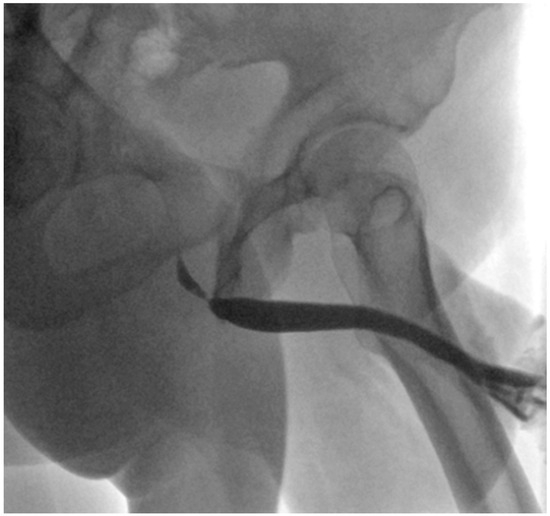

The Presentation and Treatment of Myointimoma: A Systematic Review and the First Case Report of Penile Myointimoma as a Cause of Urethral Obstruction

by Deirdre Maria König-Castillo, Armin Henning, Richard Wasicky, Clemens Kinsky, H. Christoph Klingler and Eva M. Compérat

Background/Objectives: Myointimoma is a rare, benign soft tissue tumor of the penis. We present a systematic review of the current literature and a case report of a 33-year-old male with a urethral stricture without discernible risk factors. Our aim was to investigate current [...] Read more.

Background/Objectives: Myointimoma is a rare, benign soft tissue tumor of the penis. We present a systematic review of the current literature and a case report of a 33-year-old male with a urethral stricture without discernible risk factors. Our aim was to investigate current knowledge on Myointimomas and increase the awareness of this entity. Methods: A systematic literature search was conducted across EMBASE, MEDLINE, PubMed, Scopus, Web of Science, and Google Scholar. Only 30 previously reported cases of this tumor are known—all located at the glans penis or in close proximity to it. Results: After the exclusion of non-eligible studies, 14 studies were included. Conclusions: Myointimomas are a relevant differential diagnosis in recurring cases of bladder outlet obstruction. Full article